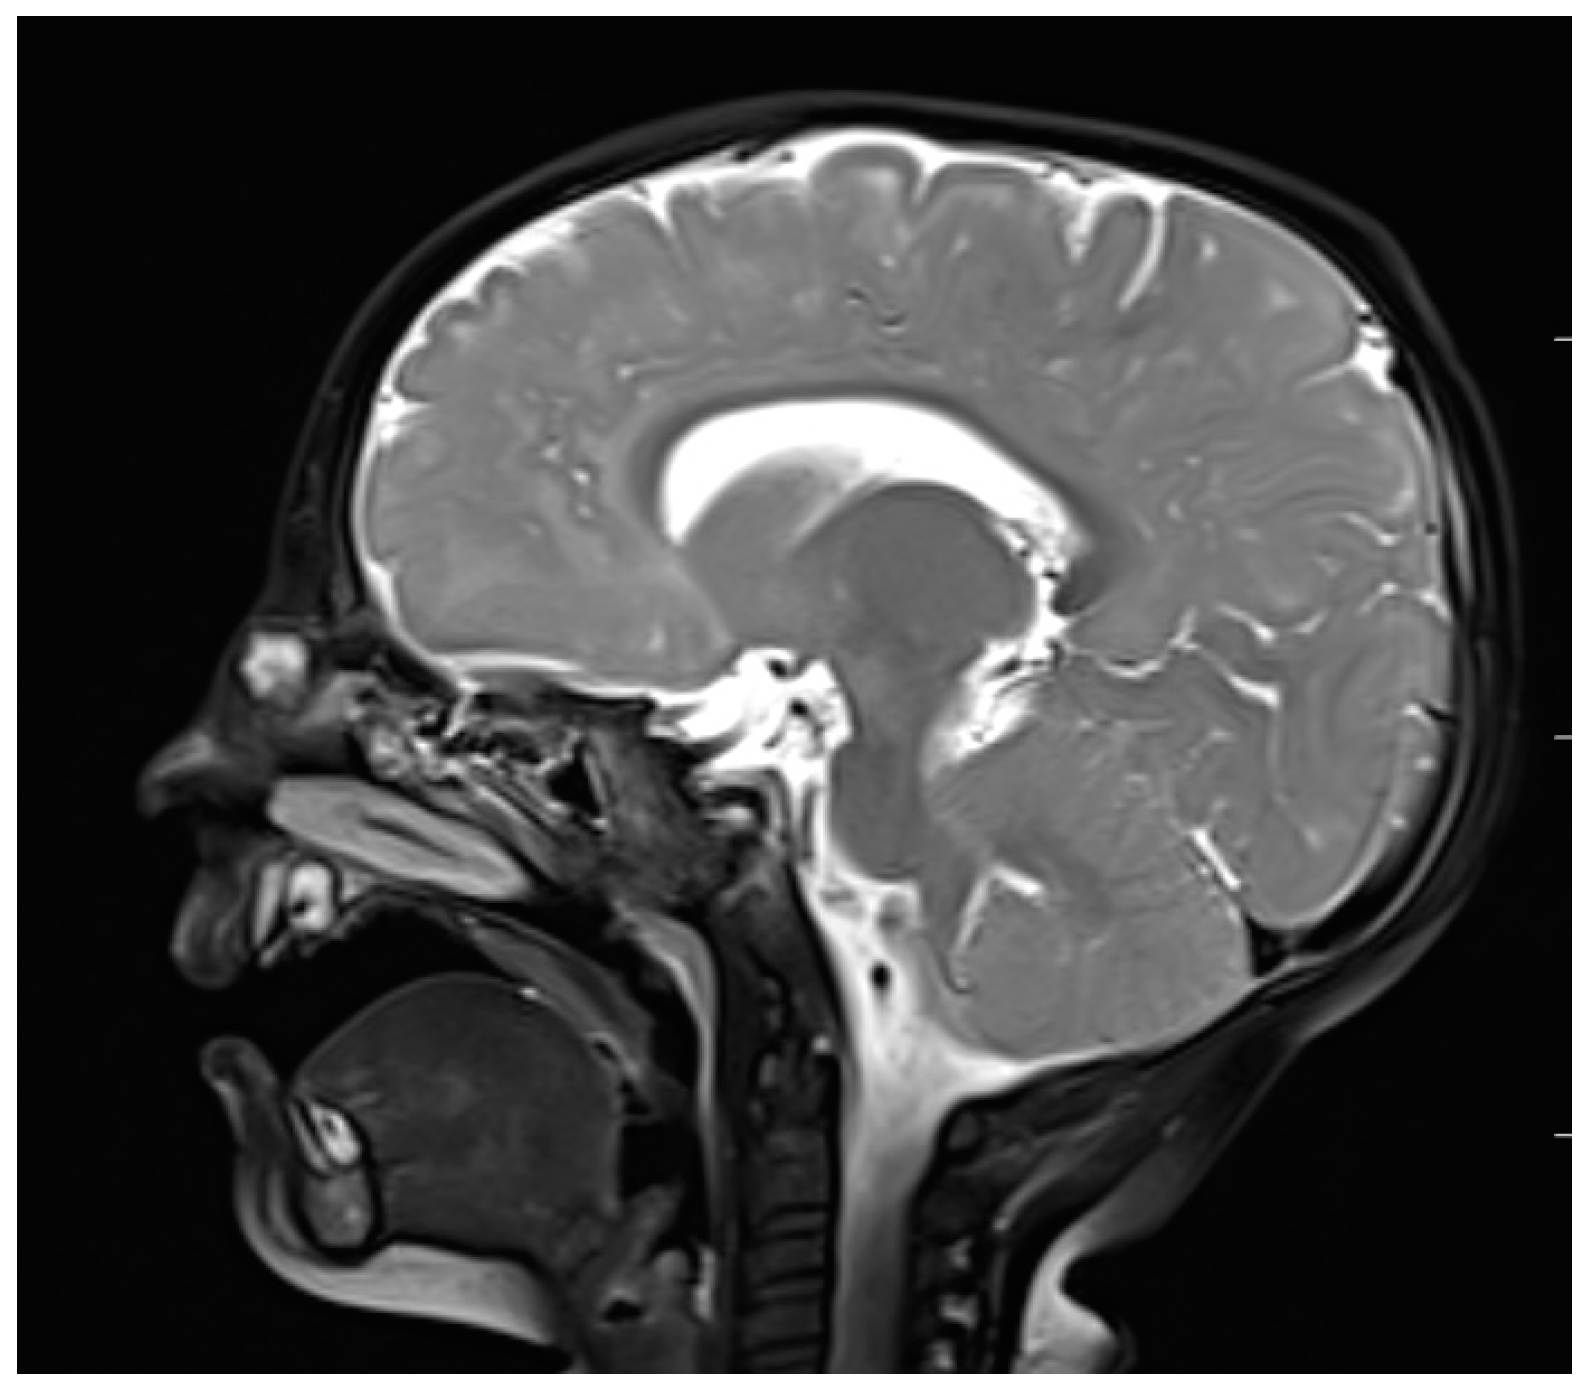

| MRI | Variable signal intensity depending on the protein content; fat-suppressed T1-weighted images—differentiation between skull base defects and enhancing non-ossified cartilage of anterior cranial fossa; DWI—typically high-signal-intensity lesion with corresponding low signal intensity on ADC maps | Discontinuity with the brain parenchyma; variable visualization of a fibrous stalk connection to CNS; well-circumscribed, rounded, or polypoid mass—isointense or rarely hypointense to gray matter on T1-weighted imaging; neural tissue—more hyperintense on T2-weighted images to normal brain parenchyma in most cases; dysplastic tissue usually corresponds with no enhancement or moderate enhancement; noticeable enhancement at the lesion periphery | Herniation of intracranial tissue and its continuity with the brain | |